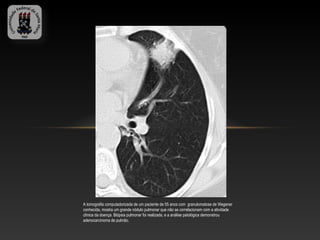

A tomografia computadorizada de um paciente de 55 anos com granulomatose de Wegener

conhecida, mostra um grande nódulo pulmonar que não se correlacionam com a atividade

clínica da doença. Biópsia pulmonar foi realizada, e a análise patológica demonstrou

adenocarcinoma de pulmão.